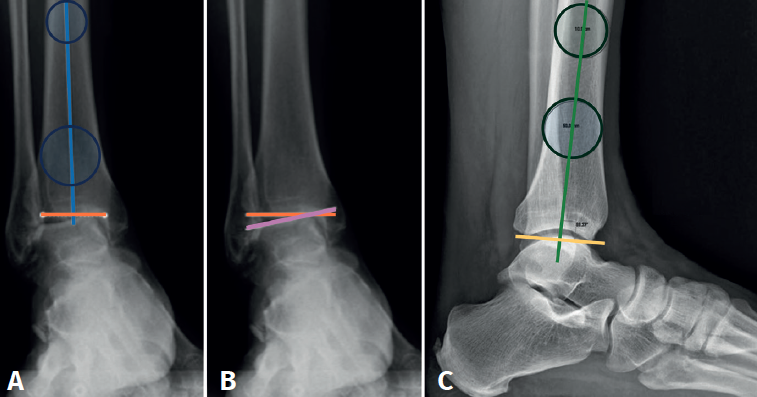

En la proyección anterior de tobillo evaluaremos el talar tilt o ángulo de inclinación del astrágalo, aumentado en las lesiones incongruentes intraarticulares (Figura 1).

reaca.32284.fs2505013-figura1.png

Figura 1. A: ángulo tibial distal anterior, entre el eje anatómico de la tibia en el plano posteroanterior y la línea de la superficie articular distal de la tibia; B: ángulo de inclinación astragalina (talar tilt), formado entre la línea de la superficie articular tibial y la línea de la superficie articular astragalina. Evalúa la congruencia articular; C: ángulo tibial distal lateral, entre el eje anatómico lateral de la tibia y la línea de la superficie articular distal lateral de la tibia.

Debemos observar si, en las proyecciones laterales, existe una traslación anterior del astrágalo que muchas veces ocurre en estos fenómenos degenerativos crónicos asociados a inestabilidades (Figura 2).

Figura 2. Traslación anterior del astrágalo, característica de las artropatías tibioastragalinas secundarias a inestabilidades crónicas.